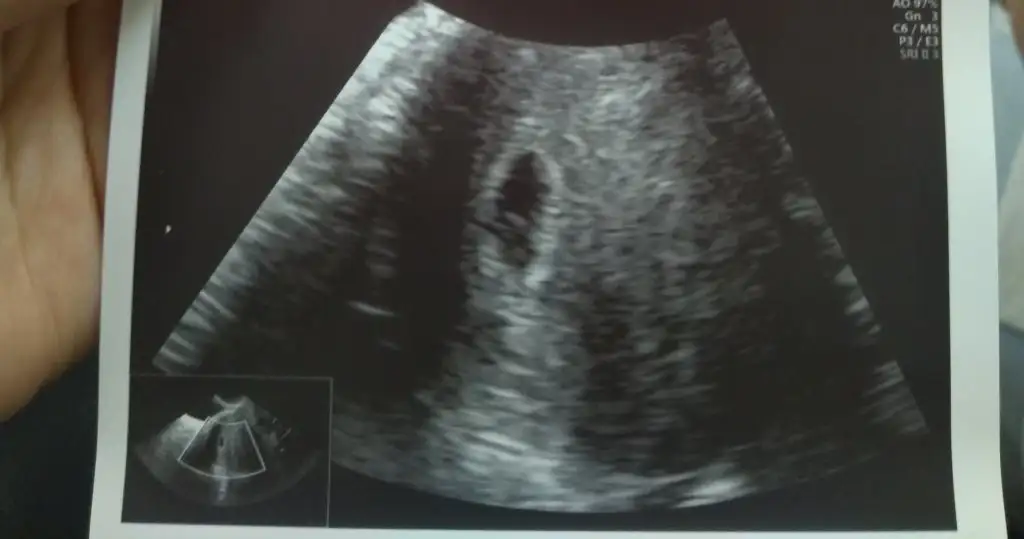

Canım vajinal ultrason du dimi sanki gerçi şu an değilde bidahaki gittiğindeki ultrason görüntüsünü atarsan daha güzel yorum yaparımm😍❤️ Karından ultrasonda plesanta soldaysa erkek sağdaysa kız. Vajinal ultrasonda tam tersi🥰